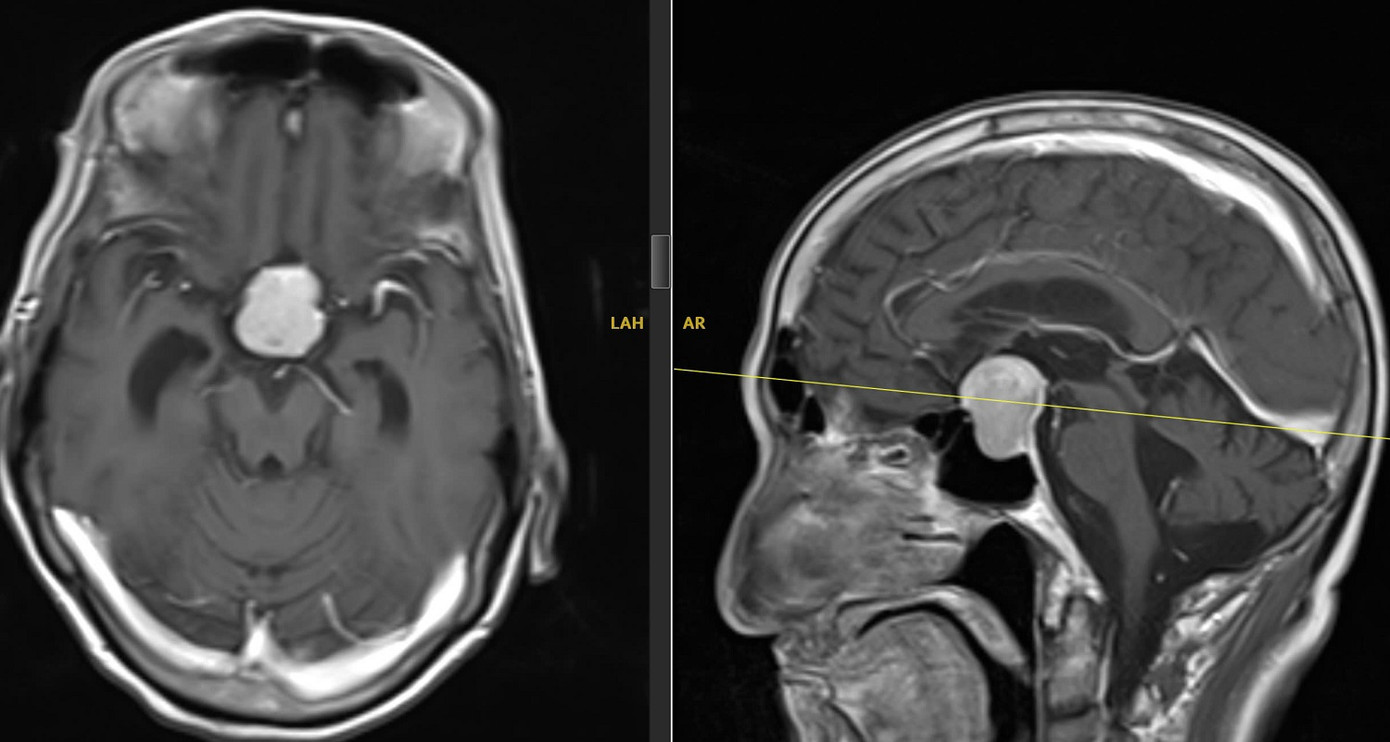

Gia đình đã đưa bà L. vào TPHCM để điều trị. Kết quả kiểm tra cho thấy bà mắc u tuyến yên kích thước 3cm, chèn ép dây thần kinh thị giác – nguyên nhân trực tiếp gây mờ mắt và đau đầu.

| Khối u tuyến yên (vùng màu trắng) là nguyên nhân khiến người bệnh mờ mắt, đau đầu |

Trường hợp thứ hai là ông N.V.H. (74 tuổi, quê Cà Mau) bị mờ mắt, đau đầu suốt hơn nửa năm. Ban đầu, ông H. đi khám tại cơ sở chuyên khoa mắt nhưng không phát hiện bất thường ở nhãn cầu. Chỉ đến khi được chỉ định chụp MRI não mới phát hiện ông H. có khối u tuyến yên lớn 3,1cm.